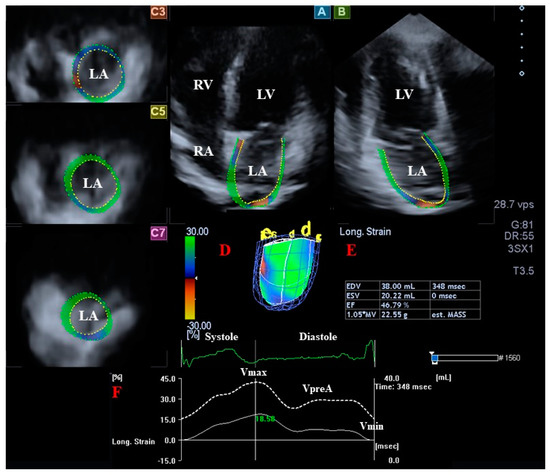

2.5. 3DSTE-Derived Determination of LA Volumes

- Vmax—end-systolic maximum LA volume, measured just before mitral valve opening (largest LA volume);

- VpreA—LA volume before atrial contraction in early diastole, at the time of P wave on ECG;

- Vmin—late diastolic minimum LA volume, measured just before mitral valve closure (smallest LA volume).